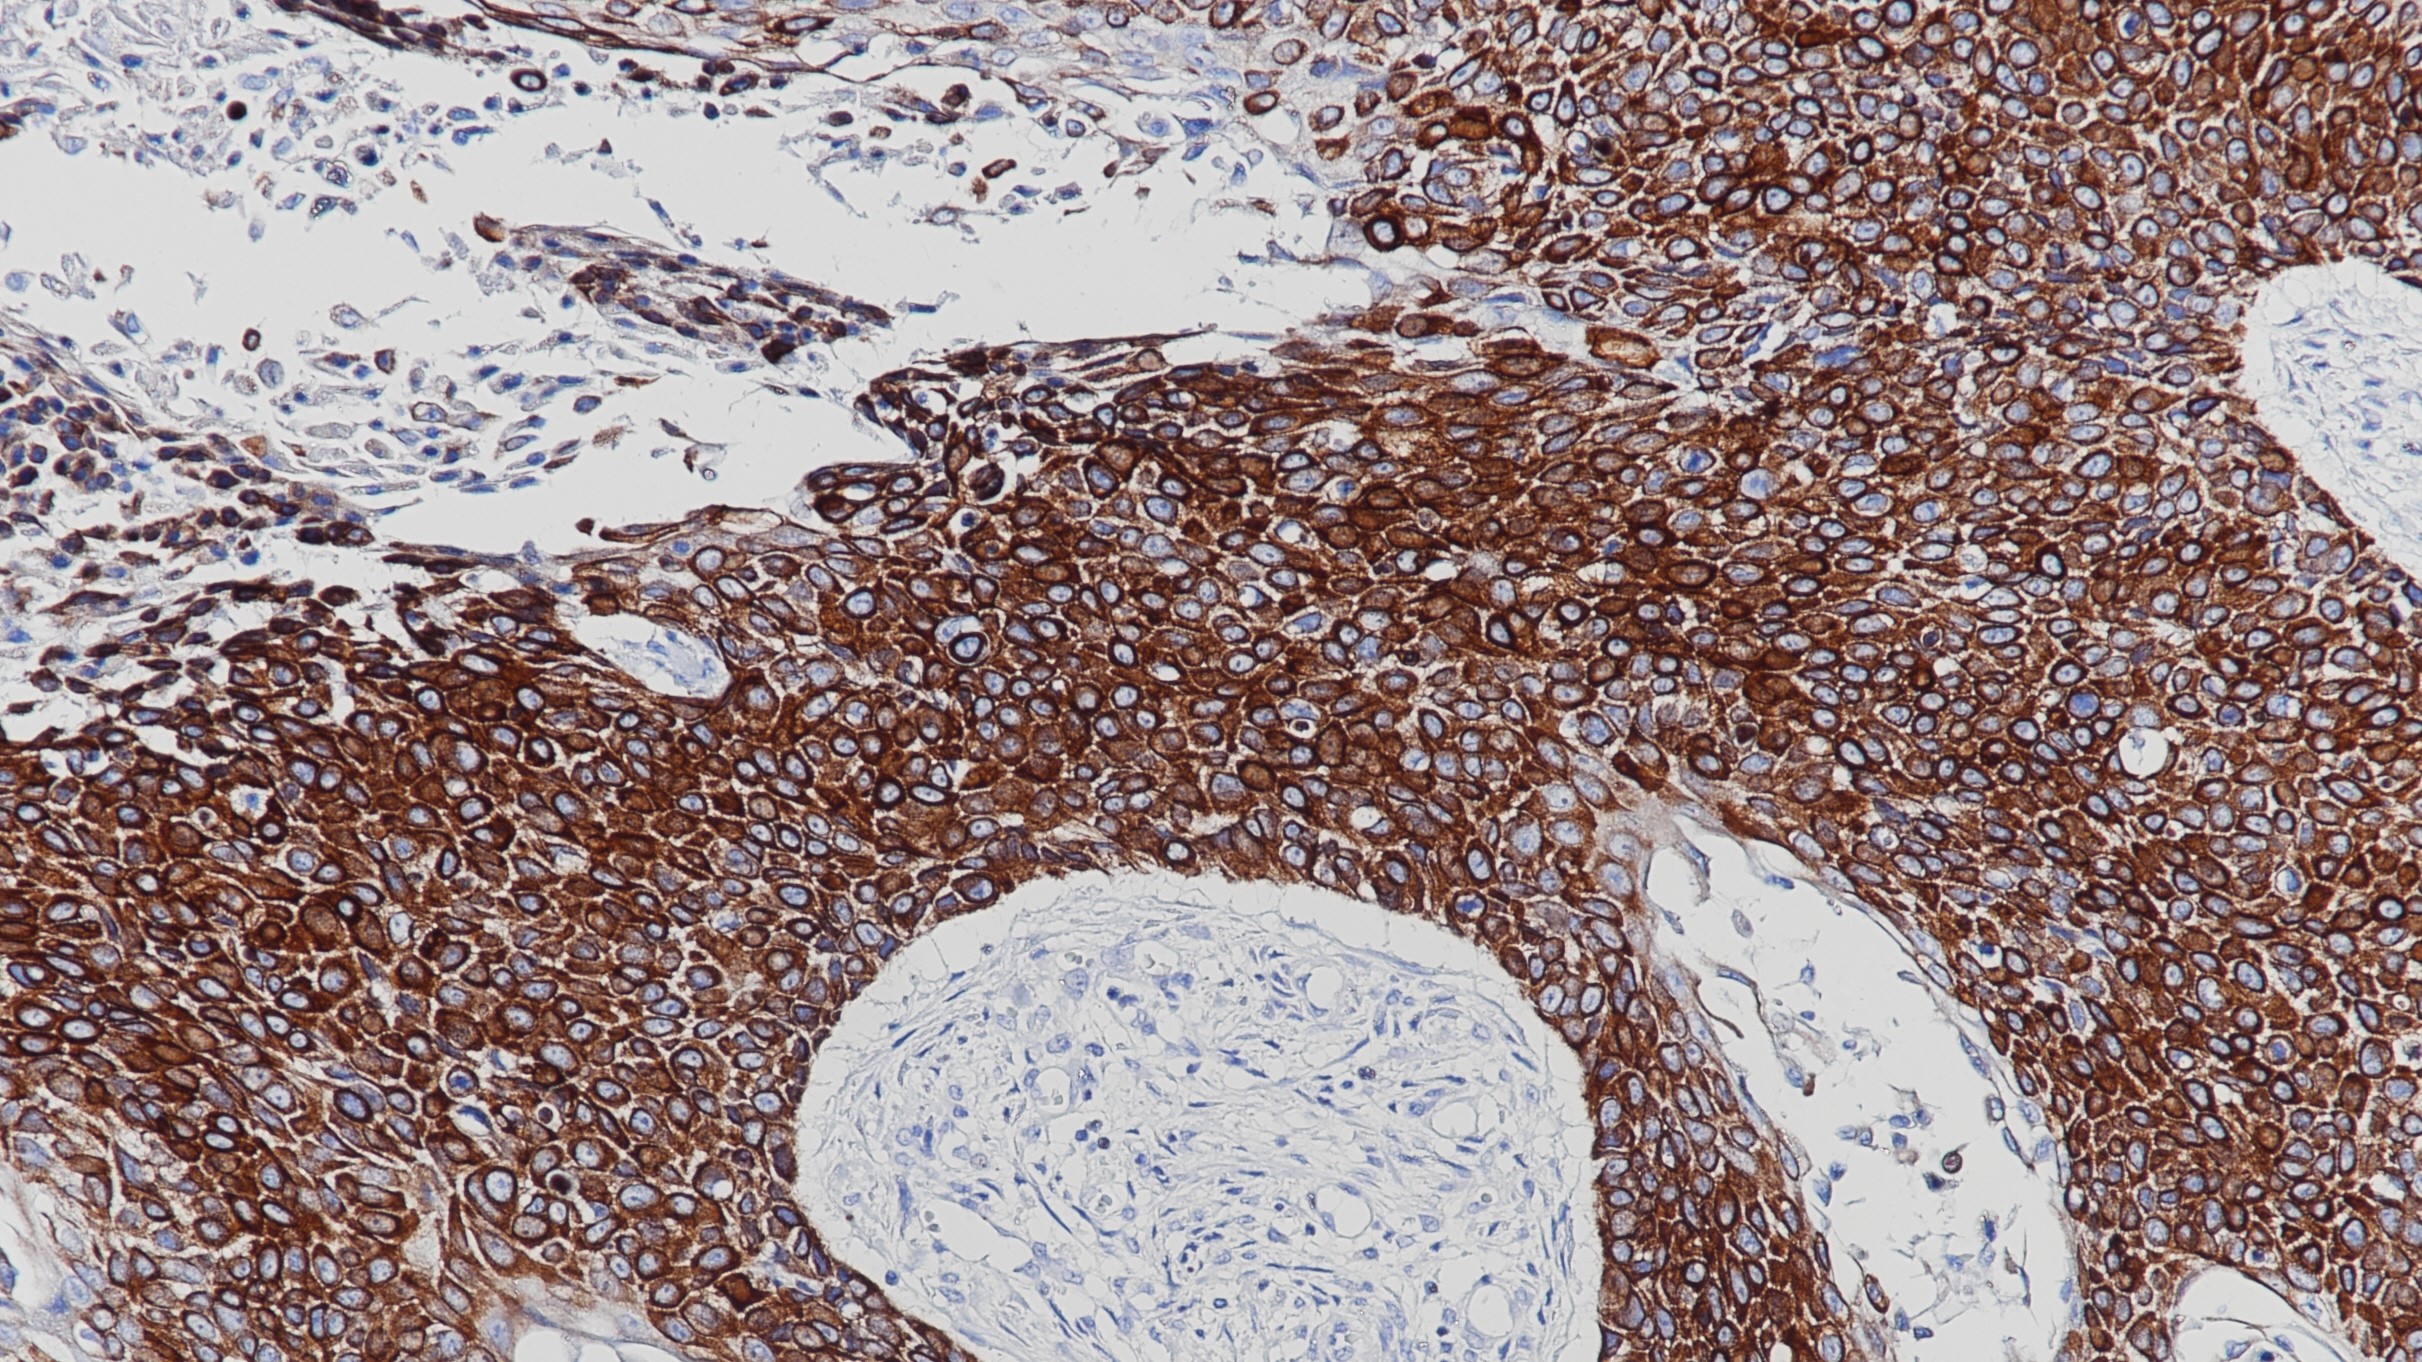

CD8抗原是一种细胞表面糖基蛋白,存在于大多数细胞毒性T淋巴细胞(CTL),作为共同受体识别与MHC I类相关的多肽TCR,并通过结合MHC来支持CTL活化,而不直接作用于多肽。CD8是CD8α和CD8β的异质二聚体,表达于细胞毒性抑制T细胞。CD8在近1/3的外周血T细胞(CD4-细胞)上表达,在自然杀伤(NK)细胞中也检测到低水平的表达。在正常的人类扁桃体中,大量的CD8+淋巴细胞存在于副皮质区,偶尔也会在生发中心的鳞状上皮中出现阳性细胞。

阳性对照

扁桃体